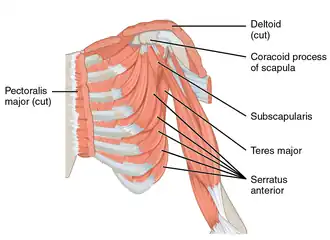

The coracoid process (from Greek κόραξ, raven[1]) is a small hook-like structure on the lateral edge of the superior anterior portion of the scapula (hence: coracoid, or "like a raven's beak"). Pointing laterally forward, it, together with the acromion, serves to stabilize the shoulder joint. It is palpable in the deltopectoral groove between the deltoid and pectoralis major muscles.

The ascending portion, flattened from the frontal aspect backward, presents in front a smooth concave surface, across which the subscapularis passes.

The horizontal portion appears flattened when viewed from above looking downward; its upper surface is convex and irregular, and gives attachment to the pectoralis minor; its under surface is smooth; its medial and lateral borders are rough; the former gives attachment to the pectoralis minor and the latter to the coracoacromial ligament; the apex is embraced by the Conjoint tendon of origin of the coracobrachialis and short head of the biceps brachii and gives attachment to the coracoclavicular fascia.

The coracoid process is a snare molded bone design projecting anterolaterally from the unrivaled(?) part of the scapular neck. Surgeons refer to this part of the body as the “lighthouse of the shoulder”[5] as it is close to the area where structures of veins and nerves (neurovascular) are bound together. The distances between the coracoid base and the neurovascular structures is like a 90 degree chair. The suprascapular ligament is right next to the coracoid process. The muscles that are attached are: Pectoralis Minor, Coracobrachialis, and Biceps Brachii.

- The pectoralis minor muscle (insertion) – to 3rd, 4th, 5th and on some rare occasions, 6th rib.

- The short head of biceps brachii muscle (origin) – to radial tuberosity.

- The coracobrachialis muscle (origin) – to medial humerus.